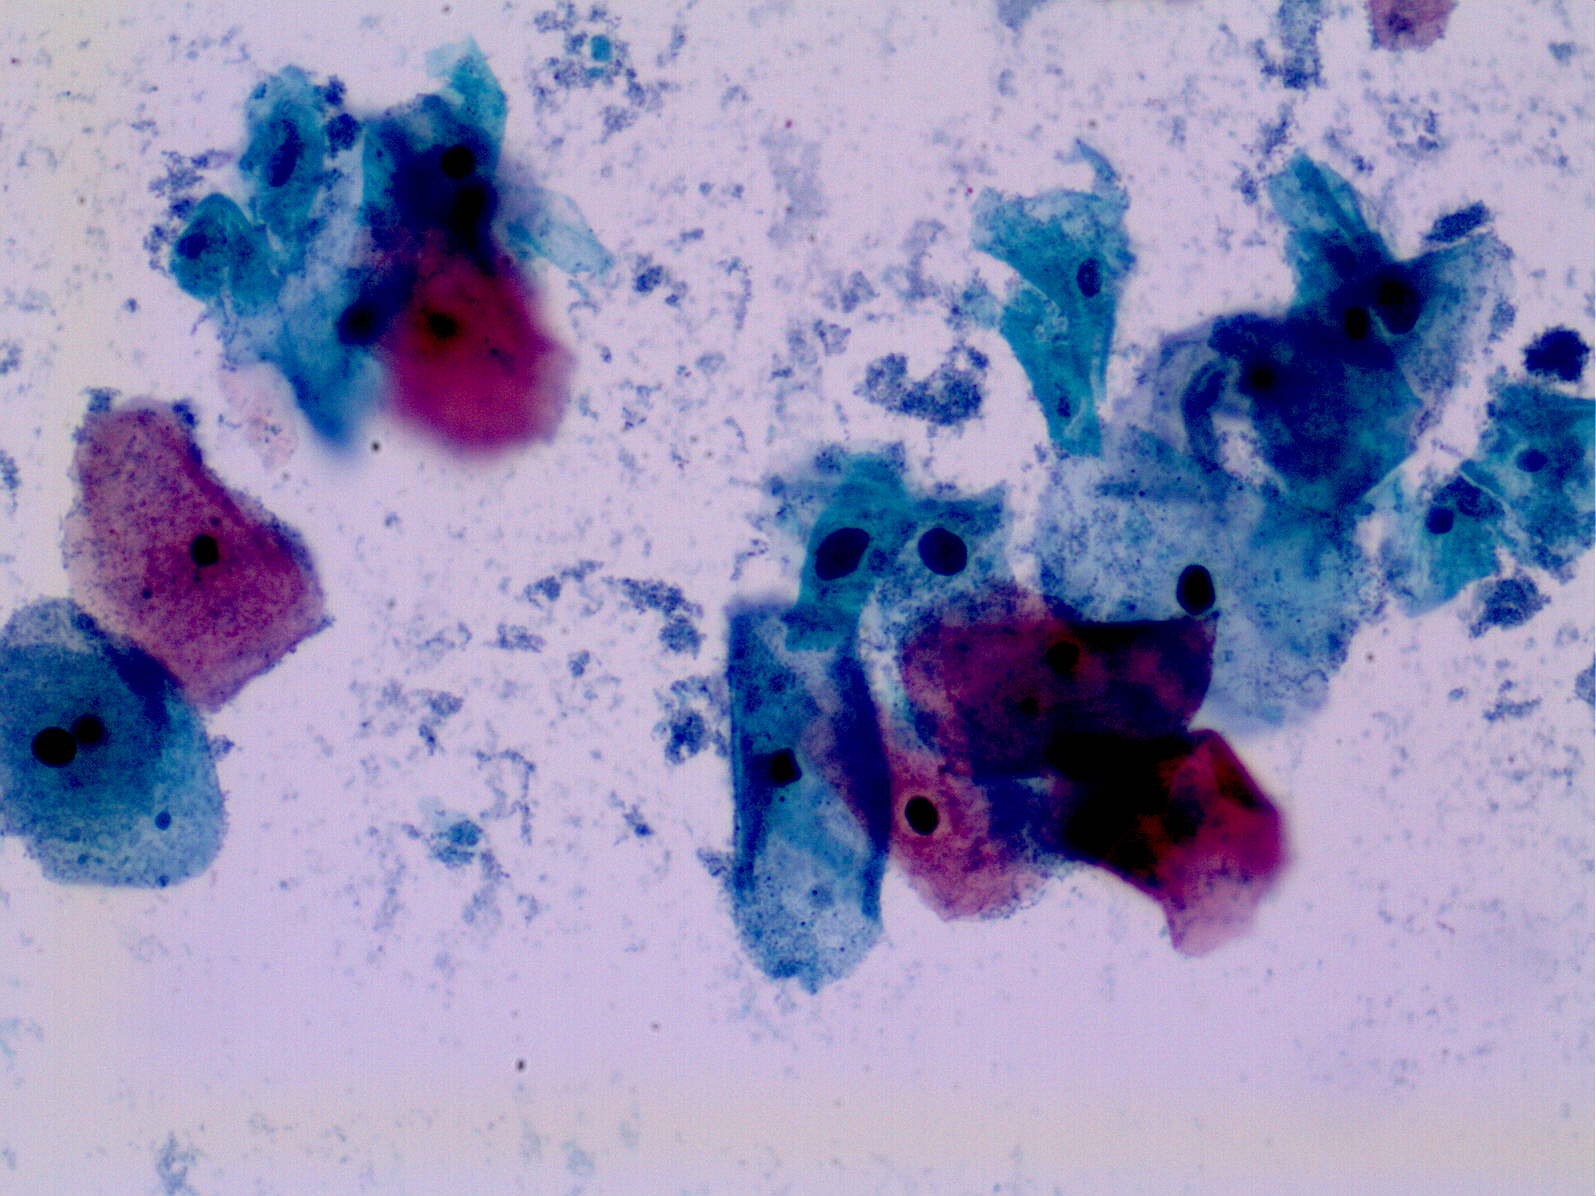

Как передается вирус гарднерелла - фото презентация